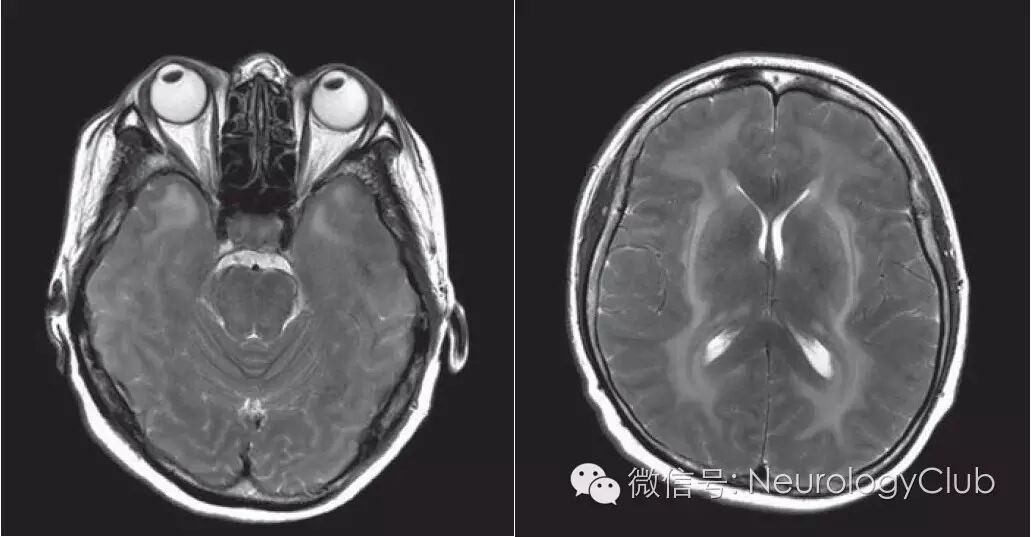

CADASIL患者在临床症状出现前即可有影像学上的改变。多对称分布,在MRI的T2像表现为大小不一的高信号,不累及弓状纤维。主要位于侧脑室周围和深部白质。以额叶白质最常受累,其次为颞叶和顶叶,而枕叶受损程度相对较轻。其中,外囊、颞极的对称性异常信号对诊断有高度提示作用。胼胝体亦可全层受累,引起胼胝体萎缩。皮层一般不受累。

疾病早期出现血管周围间隙加大,继而出现对称性孤立的单个结节状高信号区,此阶段容易与多发性硬化混淆。这些白质异常信号可以进一步扩大表现为外囊和颞极的高信号,对于年龄在20-30岁的亚临床患者,其颞极白质以及侧脑室周围出现帽状异常信号是其最早期的改变。随着病程进展双侧半球白质内大片长T2信号区相互融合,晚期小脑和脑干也受累及,约半数患者出现脑干长T2信号,其中脑桥(100%)比中脑(68%)和延髓(35%)更易受累,这一现象与年龄增长相关,出现双侧脑干病灶的CDADASIL患者可能预后不良。

颞极白质T2/FLAIR呈高信号是CADASIL的特征性表现,也称为O’Sullivan征,在 皮质下动脉硬化性脑病中无此现象,对本病的诊断敏感度为89%,特异度为86%。但O’Sullivan征对中国人CADASIL诊断并不是敏感指标。

外囊受累是CADASIL的另一特异征象,表现为T2/FLAIR高信号,诊断CADASIL的敏感度和特异度分别为93%和45%,并有助于CADASIL与其他小动脉疾病的鉴别诊断。本病也可累及基底节区内囊前肢额桥束,如外囊钩状纤维束和内囊前肢同时受累,在T2/FLAIR横轴位图像高信号呈“人”字征(Herringbone pattern)。

(图3:T2WI可见CADASIL特征性的颞极高信号和外囊受累)

(图4:MRI上可见颞极、脑室旁和深部白质病变)

(图5:A:T1WI可见脑室旁低信号病灶;B-C:FLAIR可见脑室旁高信号病灶,外囊受累,基底节区可见腔隙性梗死)

(图9:A:颞极高信号病变;B:皮质下、外囊高信号病变;C-D:两例患者均有胼胝体受累[箭头])